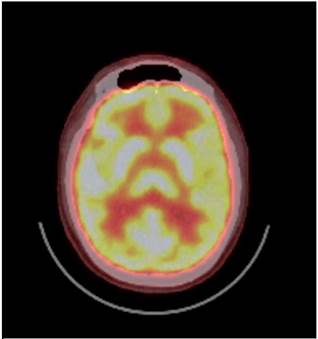

Se hizo nueva resonancia magnética cerebral simple normal (figura 1), se complementó además con tomografía por emisión de positrones normal (figura 2).

PET

Figura 2: PET